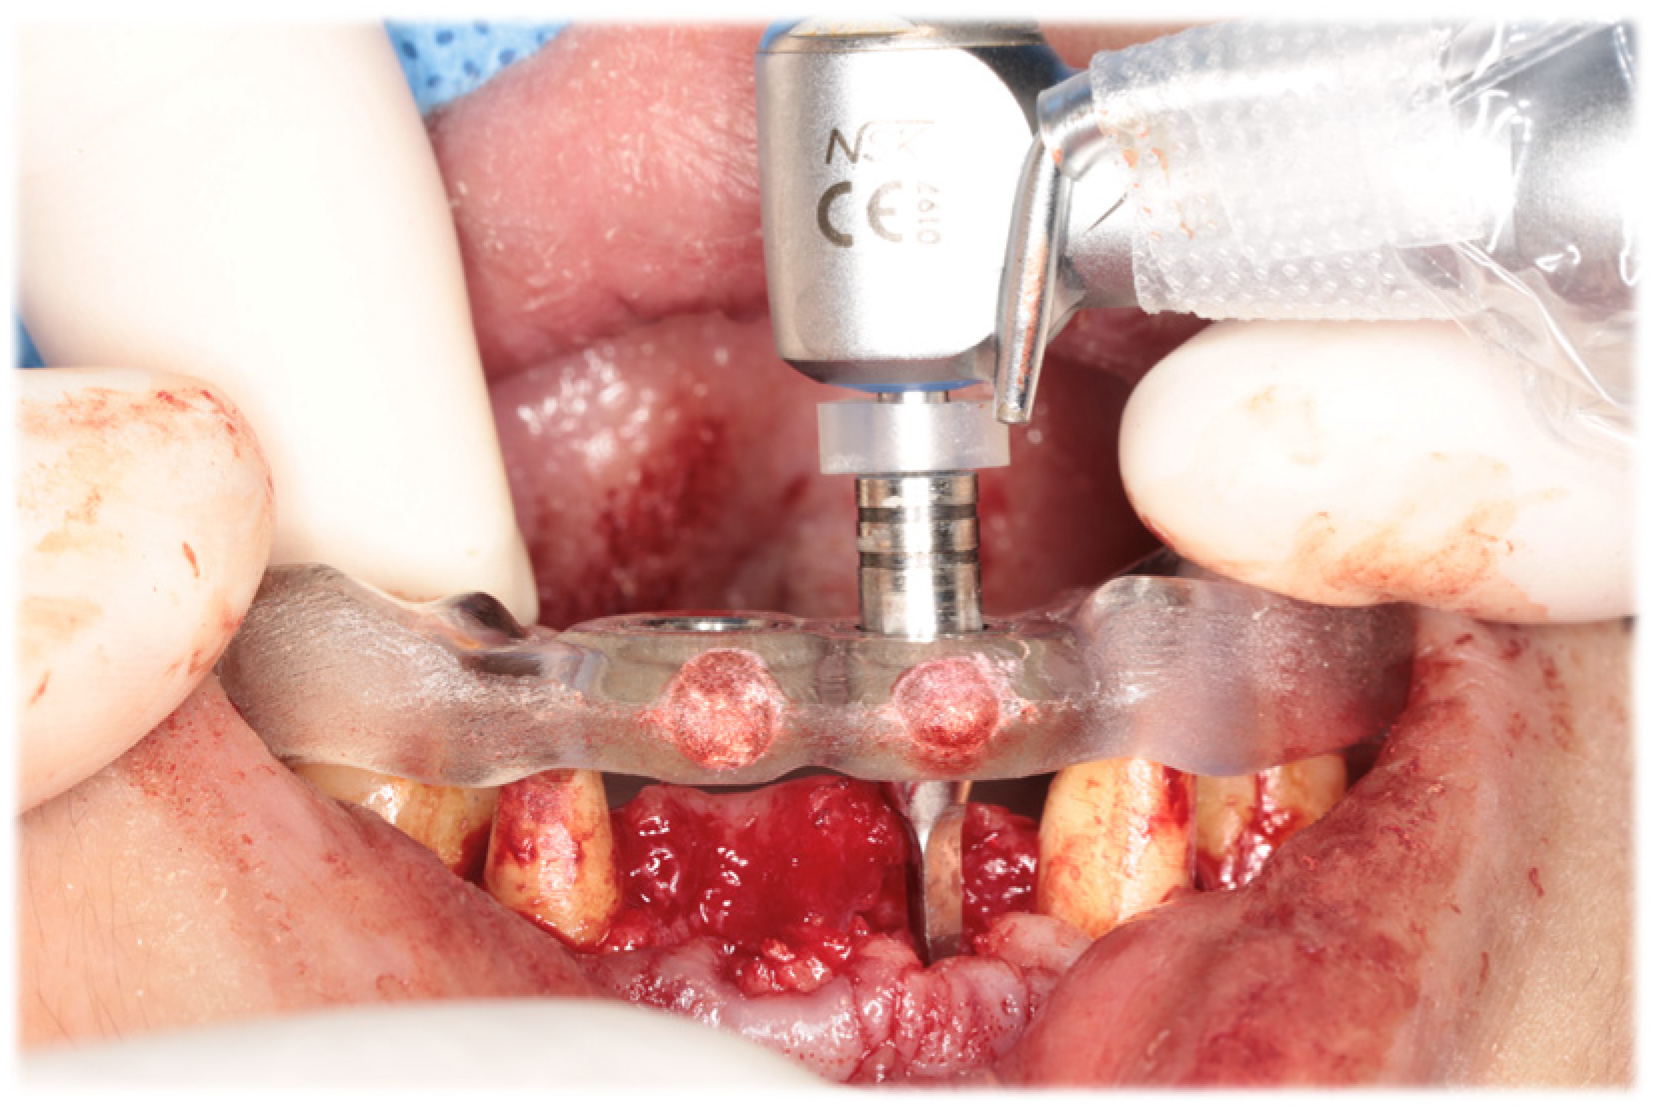

At the time of the initial examination, the porcelain-fused-to-metal restorations of the maxillary bilateral central and maxillary left lateral incisors were detached, and the maxillary left lateral incisor was affected by caries (Figure 1). A sinus tract was found on the buccal side of the maxillary right central incisor. Crowding was also observed in her dentition. The maxillary bilateral second molars had been extracted, and the maxillary right first molar and mandibular bilateral first molars were under treatment, resulting in a significant decrease in occlusal support in the molar regions (Figure 1 and Figure 2). Periodontal examination revealed extensive plaque accumulation throughout the dentition, with a plaque control record of 75% (Figure 3a). Periodontal pockets of 6–7 mm and suppuration were observed in the maxillary bilateral central incisors. Radiographs showed radiolucency around the roots of the maxillary bilateral central incisors and a fracture line around the center of the roots (Figure 3b). Marked alveolar bone resorption was observed around multiple teeth, including the maxillary bilateral lateral incisors. Based on the examination results, the patient was diagnosed with bilateral maxillary central incisor root fracture, malocclusion (classified as Angle class 1 with crowding), and stage 4 periodontitis (grade C).

Following the completion of prosthetic treatment, maintenance appointments were scheduled every 3 months. After a 5-year maintenance period, the gingival tissue showed no significant alterations in shape or color, and the adjacent teeth maintained proper functionality (Figure 12). The periodontal status of the patients changed minimally immediately after the placement of the final prosthesis and at the 5-year follow-up (Figure 13).

Figure 3. Results of initial periodontal examination (a) and dental radiographs (b).

Figure 13. Periodontal examination immediately after placement of the final prosthesis (a) and at the 5-year follow-up (b).